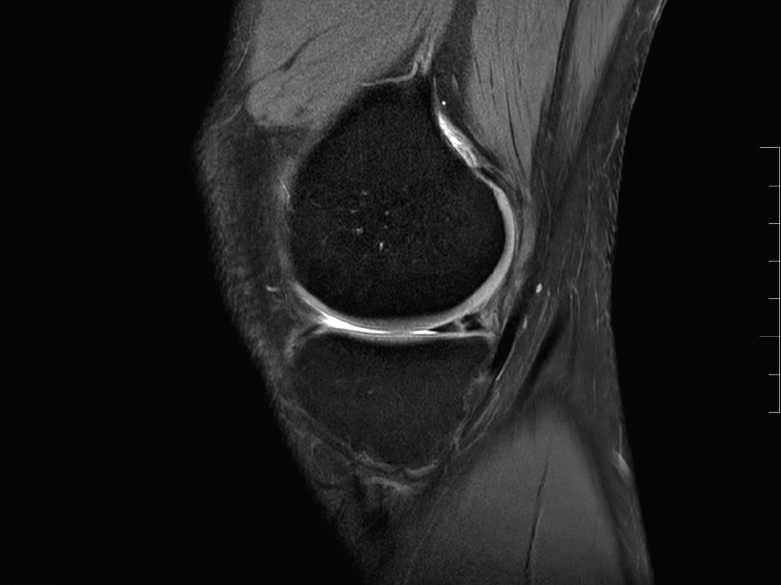

La resonancia magnética puede ser útil en la detección de la lesión de rampa, pero es sabido que cuenta con una baja sensibilidad(28).

Signos de rotura de la raíz del menisco para buscar en la resonancia magnética son la extrusión del menisco, el edema de médula ósea (MO) subcondral y el signo “fantasma”.